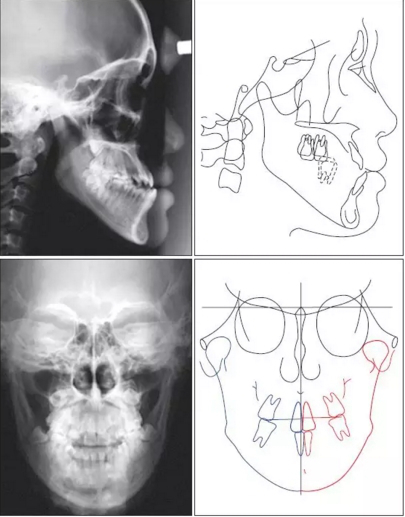

患者側(cè)貌為凹面型。頭側(cè)分析顯示,患者為骨性III類,下頜前突(Pog to N-perpendicular, 10.8 mm; ANB, −5.8°),上切牙前傾(upperocclusal plane to upper incisors, 51.0°),切牙后傾(lower occlusal plane to lower incisors, 80.5°),合平面平坦(upper occlusal plane to FH, 7.5°)。口內(nèi)檢查,患者為III類咬合關(guān)系,前牙和后牙反合,上頜第二磨牙伸長(zhǎng)。全景片顯示,第三磨牙阻生。頭顱正位片顯示由于右磨牙過(guò)度萌出導(dǎo)致合平面傾斜?;颊呦骂M向左偏斜,下牙列中線左偏。由于牙槽橫向補(bǔ)償,上切牙向左側(cè)傾斜。

根據(jù)上述發(fā)現(xiàn),患者被診斷為骨性III類錯(cuò)頜畸形,下頜前突,面部不對(duì)稱。